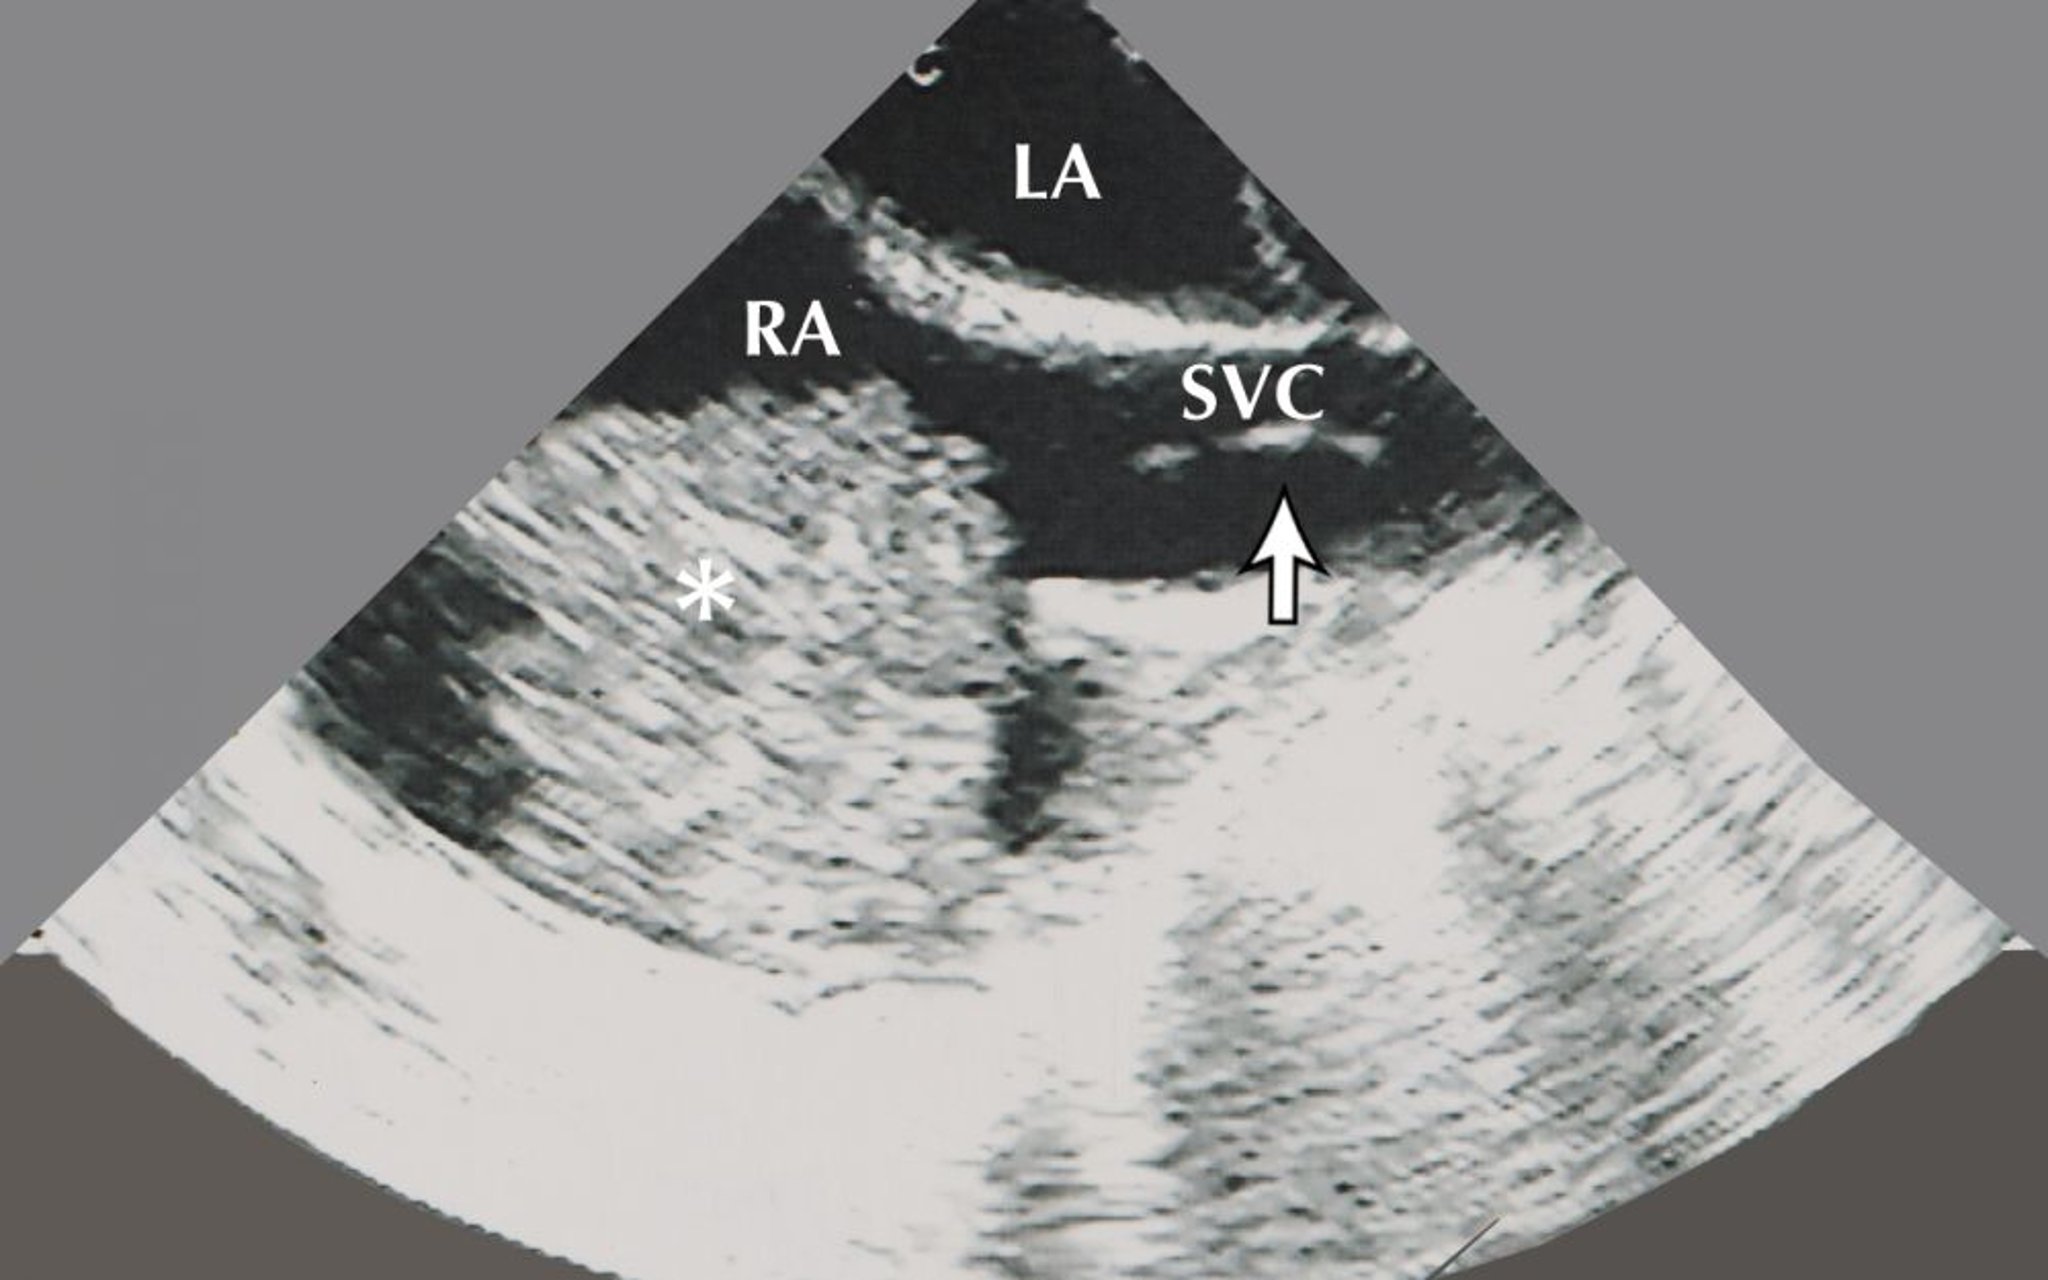

心房粘液腫(心エコー像)

この画像には,右房(RA)の心房粘液腫(アスタリスク)が示されている。この心エコー画像では,左房および上大静脈(SVC)に挿入された生検鉗子(矢印)も認められる。